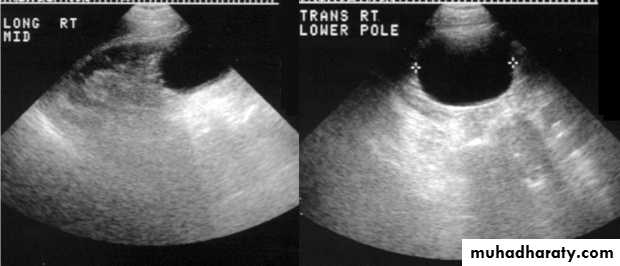

US :-

shows echo-free cystic lesion with posterior enhancement.